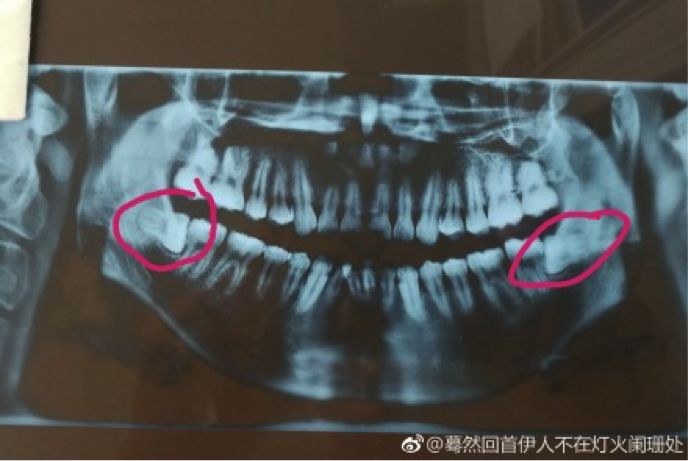

拔智齿之前要拍牙片。下面这位,您的阻生智齿长得可真周正:

蓦然回首伊人不在灯火阑珊处

啊啊啊啊啊啊,今天刚去医院看了